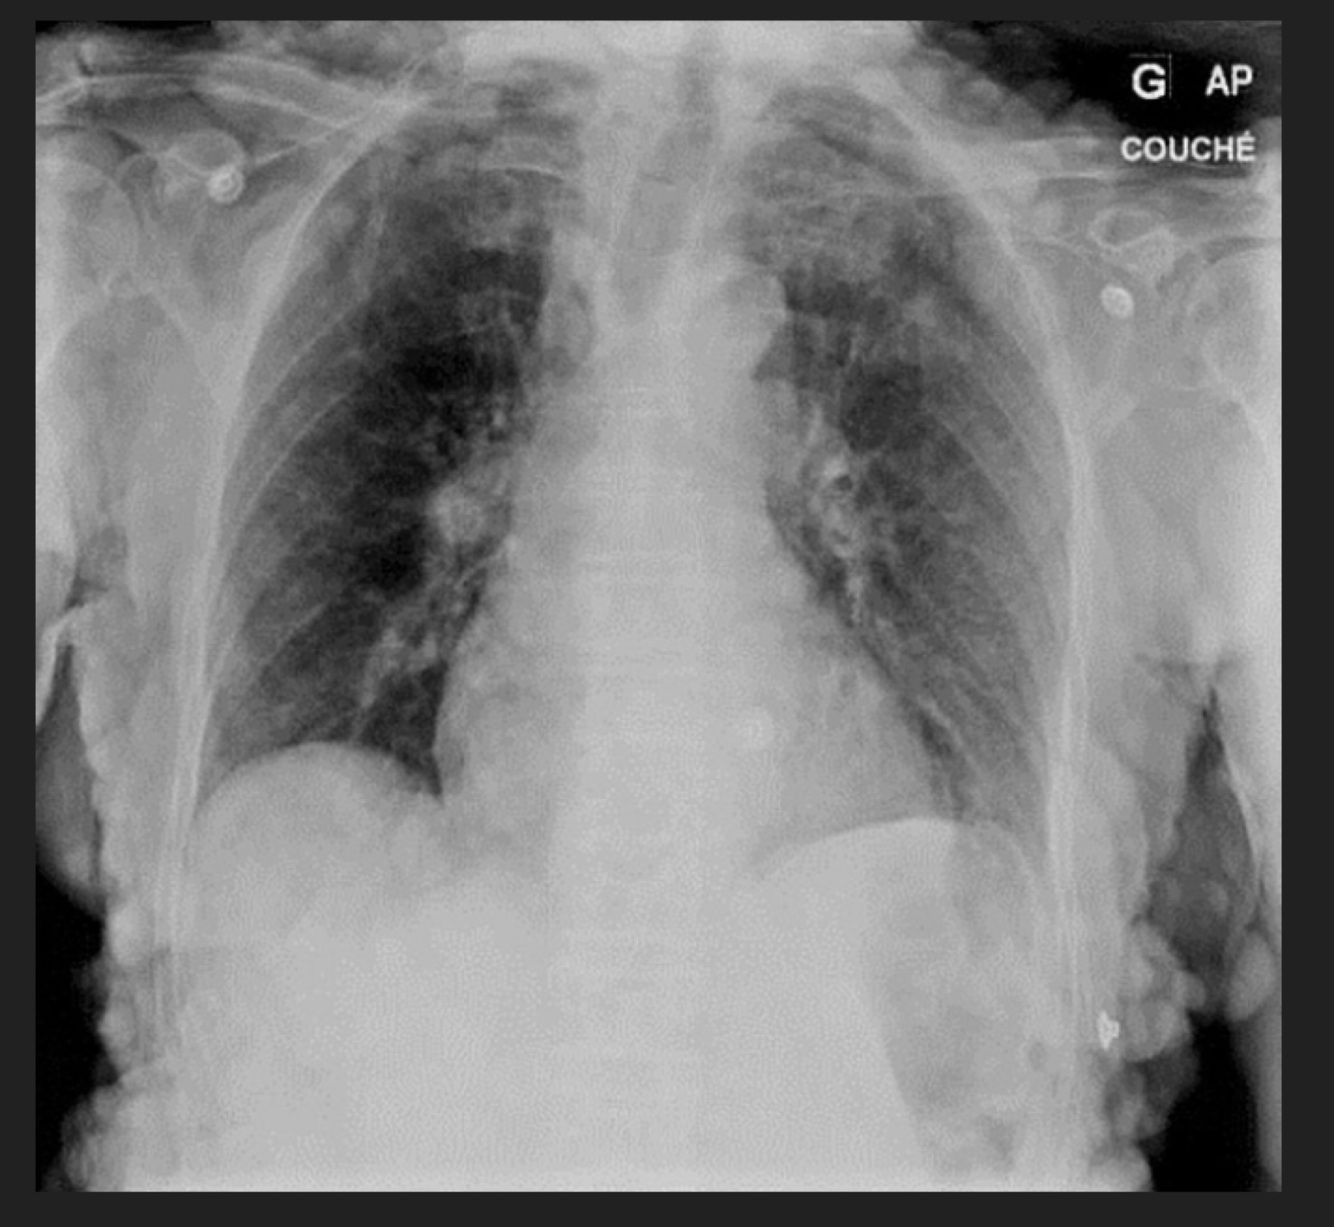

Q

Masculino de 66 años de edad, cuenta con el diagnóstico de VIH positivo, con fiebre, disnea

A

TB Miliar